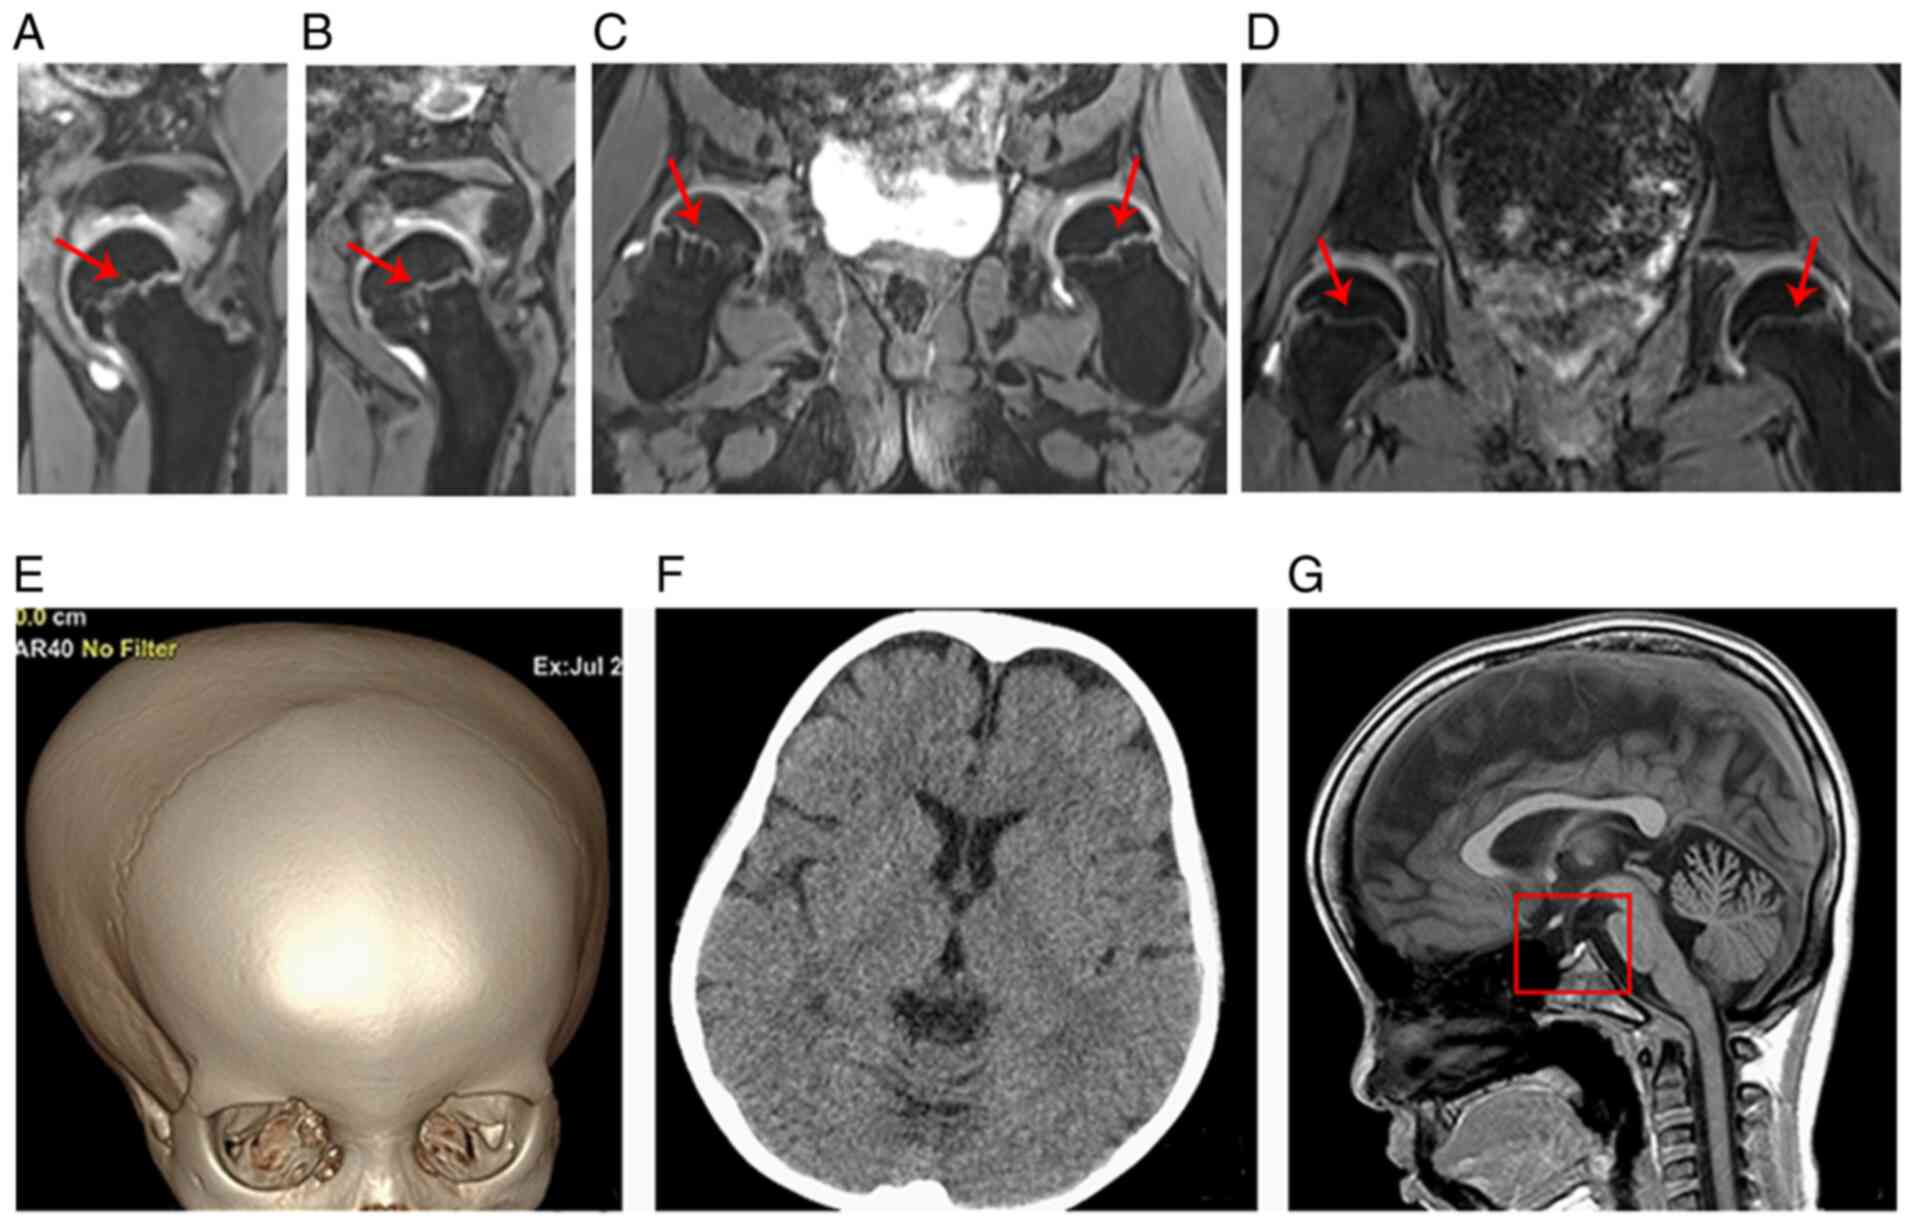

At the age of 7 years and 8 months, the patient was subjected to spiral computed tomography (CT) and the results showed that the bone density of the femoral neck was uneven (patchy high or low density) and that the femoral neck was thicker and shorter than those of the age- and gender-matched control (Fig. 4A-F). The three-dimensional double-echo steady state with water excitation MRI of the hip further revealed that the thickness of the proximal femoral epiphyseal plate was uneven and that the metaphysis of the proximal femur showed a stripe-like hyperintensity (such hyperintensity was continuous to the adjacent epiphyseal plate) (Fig. 5A-C). Fig. 5D shows the normal hip MRI of the age- and sex-matched control in coronal view. The three-dimensional volume rendering of the cranium identified the disproportionate cerebral and facial cranium as trigonocephaly, and the brain CT scan showed that the bilateral frontal extracerebral space was widened (Fig. 5E and F). The brain MRI indicated that the sella was flat and exhibited hook-like changes (Fig. 5G).

Figure 5.

Three-dimensional double-echo steady state with water excitation MRI of the hip and imaging of the head. (A and B) Bilateral sagittal and (C) coronal views of the hip demonstrated that the thickness of the epiphyseal plate was uneven with stripe-like hyperintensity as indicated by the red arrow. (D) Normal hip MRI of the age- and sex-matched control in coronal view. (E) Three-dimensional volume rendering of the cranium presented trigonocephaly. (F) The brain computed tomography scan (transverse view) demonstrated the widened bilateral frontal extracerebral space. (G) T1-weighted image from the brain MRI (sagittal view). The red square indicates the flat sella. MRI, magnetic resonance imaging.